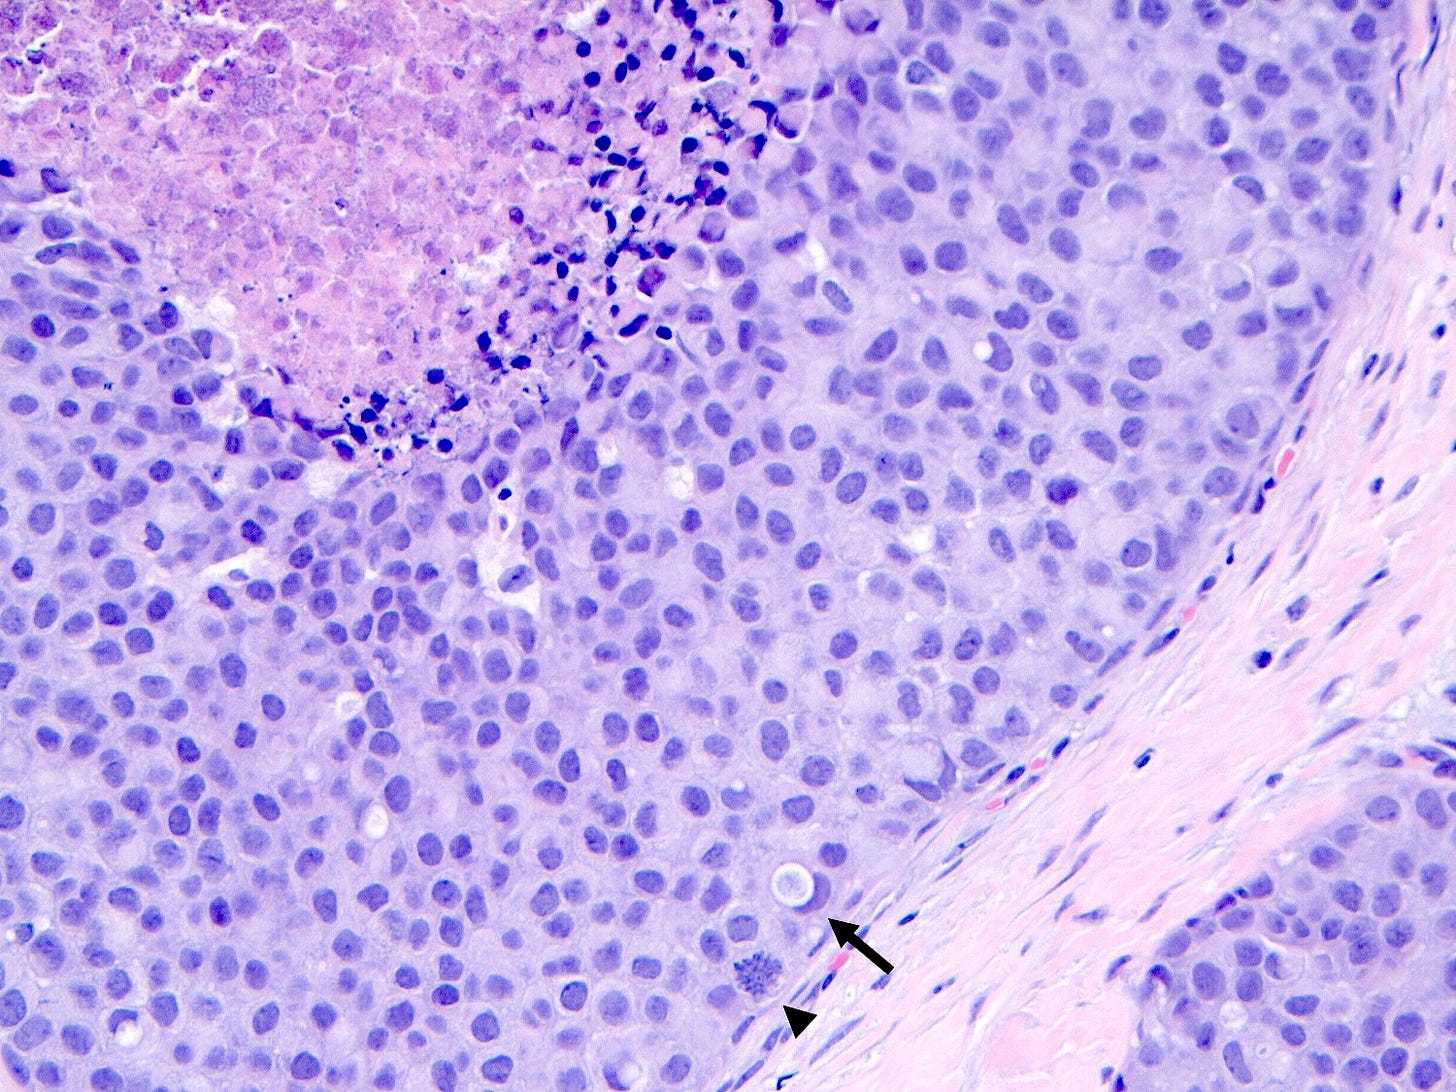

Florid lobular carcinoma in situ - microscopic images

Florid LCIS is a rare (< 5% of LCIS) nonclassical or variant form of lobular carcinoma in situ in which acini and ducts are markedly distended with little to no intervening stroma. It may have a mass-like architecture and includes cells with cytologic features of classic LCIS (type A or type B cells) with or without comedonecrosis and calcifications. Most cases are associated with classic LCIS or atypical lobular hyperplasia (ALH).

Florid LCIS has features of a high risk precursor lesion of invasive carcinoma including a higher upgrade rate, increased association with invasive carcinoma and more genetic complexity compared to classic LCIS.

In contrast to classic LCIS, complete surgical excision of florid LCIS is recommended.